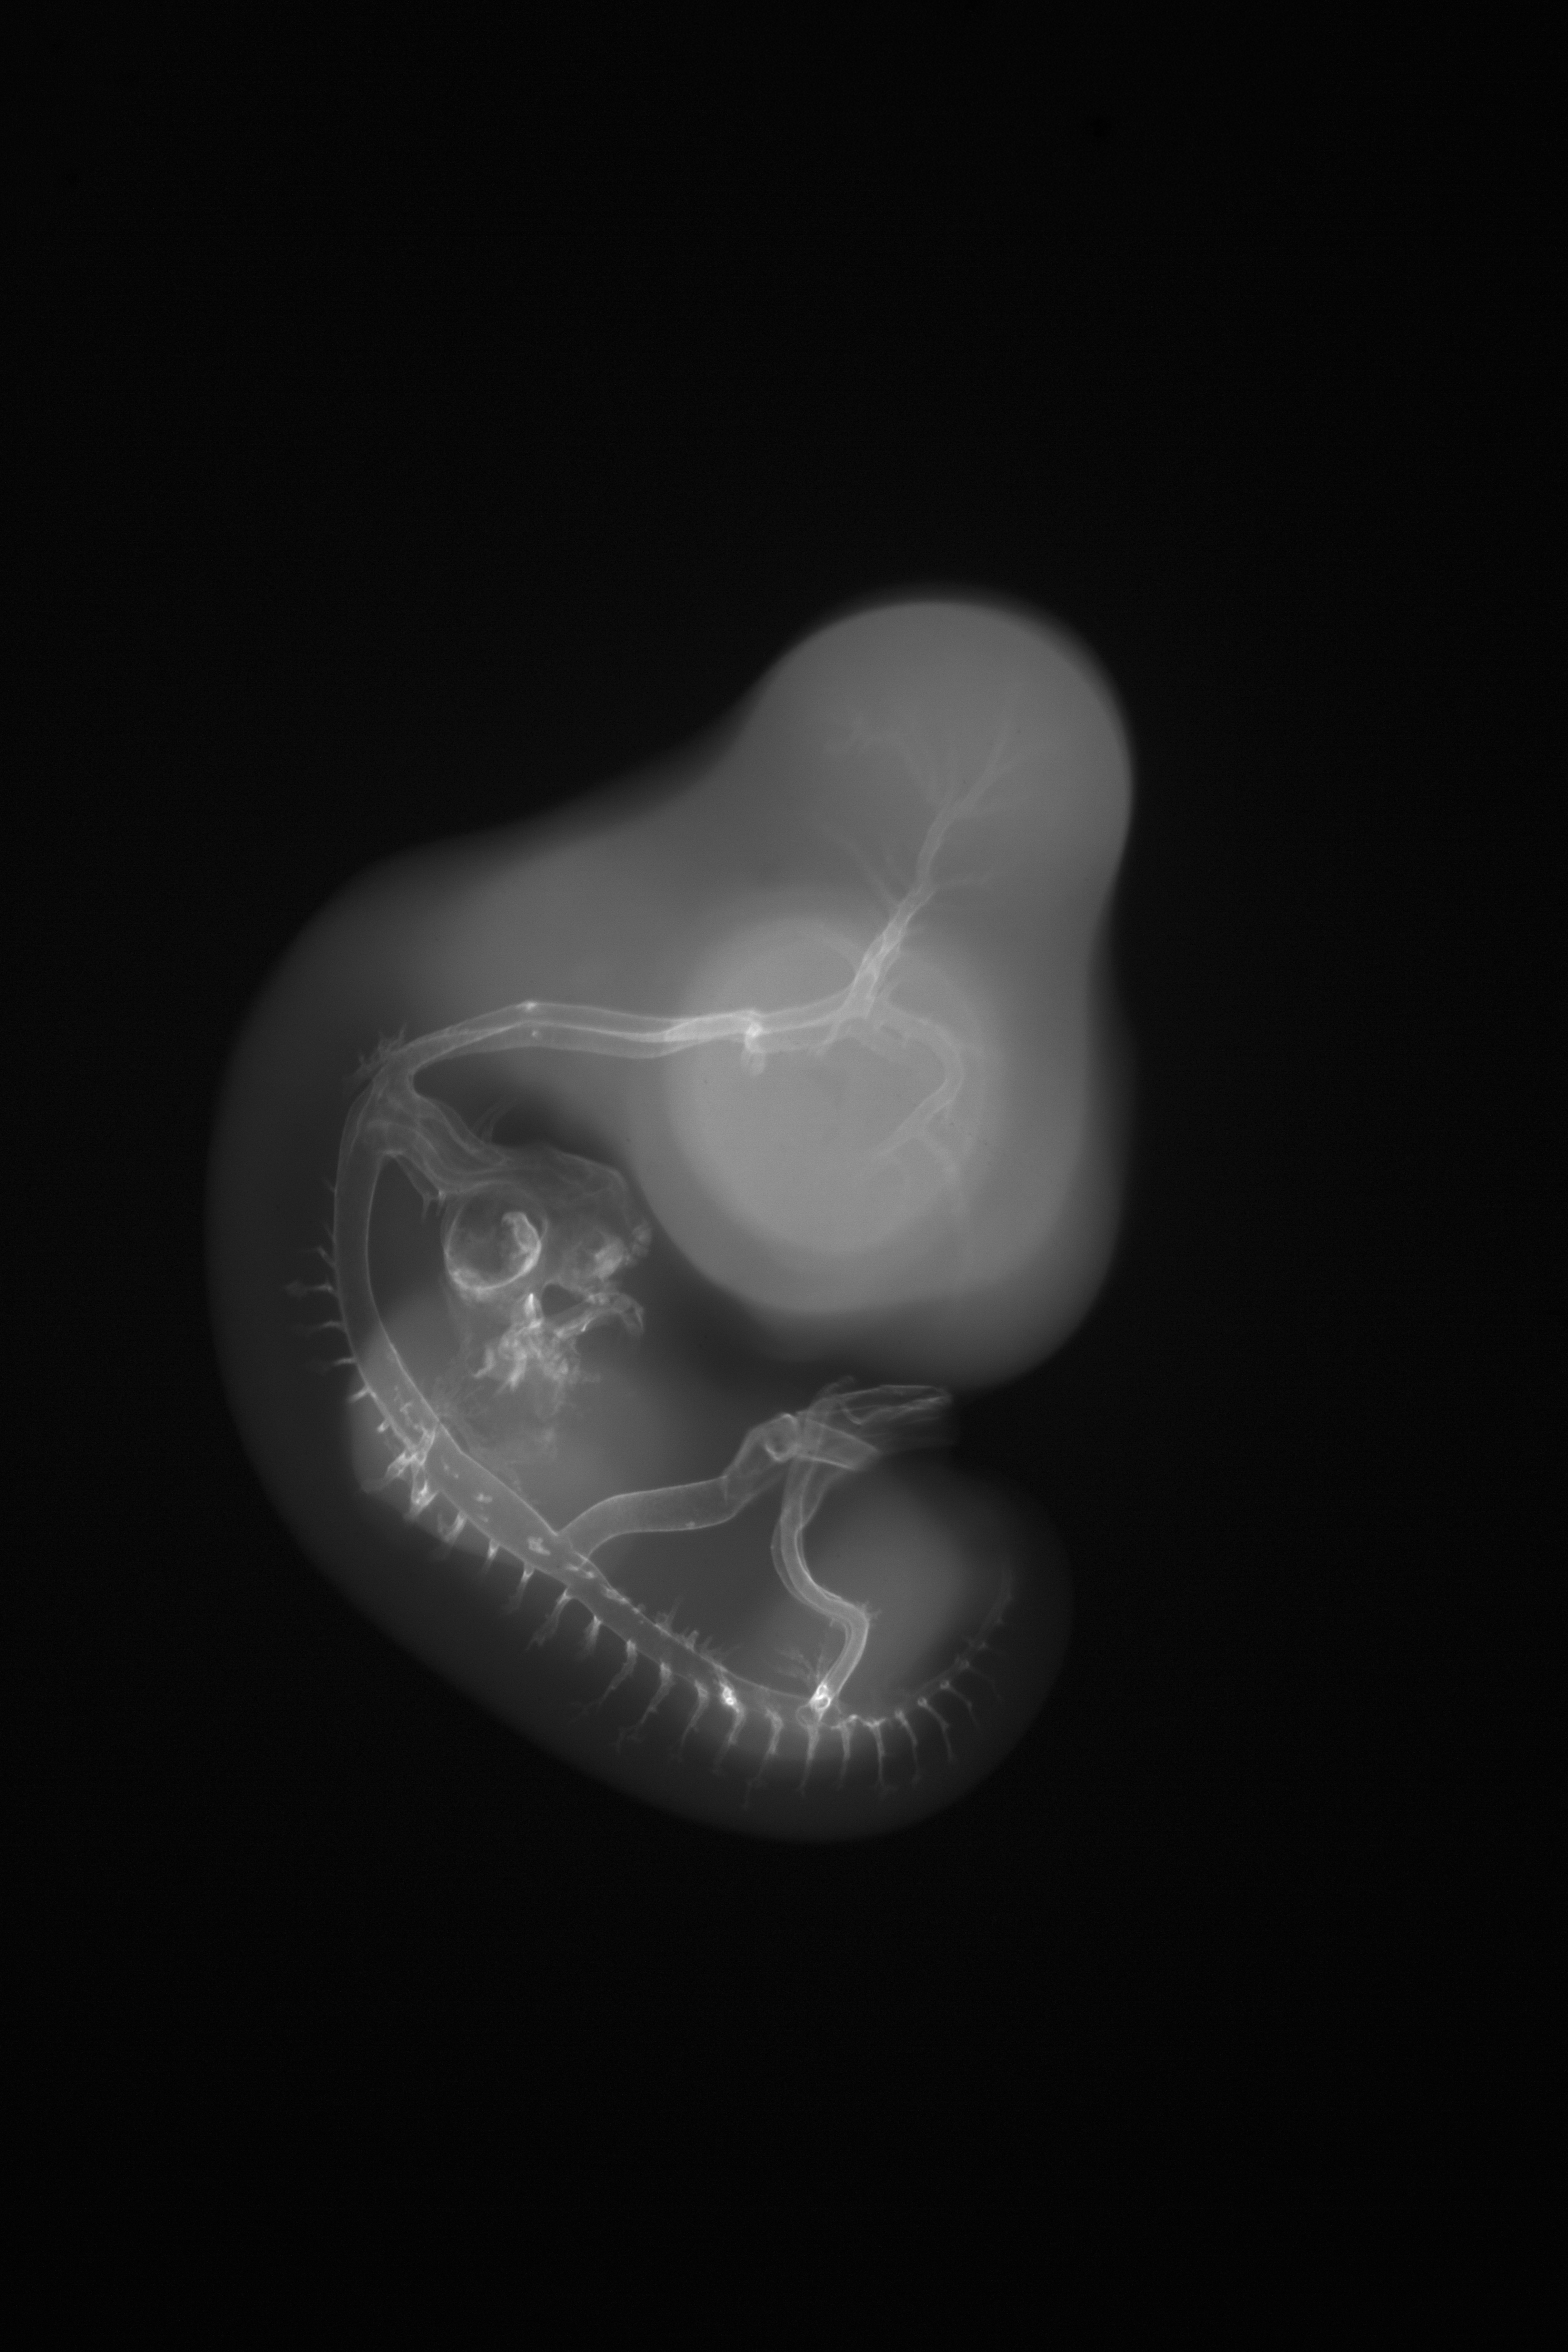

Chick Embryo Microangiography

Hamburger-Hamilton (HH) Stage 26 (approx. 5 days)

X-Ray Micrographs